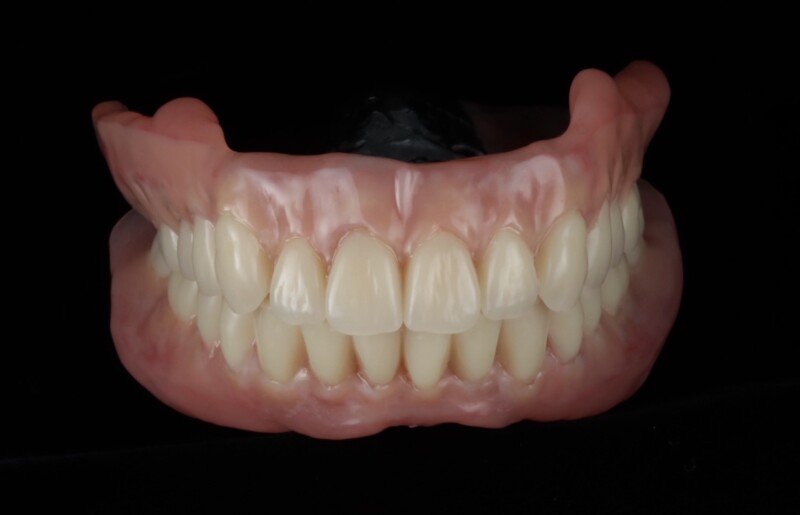

歯肉の質感まで再現された最終精密義歯

天然歯と見分けがつかない最終精密義歯

インプラントなしでも、ここまで動かない総義歯

- 真っ直ぐ噛んでも、横に歯を擦るように動かしても安定していることが左の動画で確認することができます

最終的には、入れ歯の安定性が向上し、食事の際のズレや不安も軽減され、日常生活における「噛める」という機能を取り戻すことができました。

「不安な時期もあったが、今は治療して本当に良かった。今までで一番快適な入れ歯です」